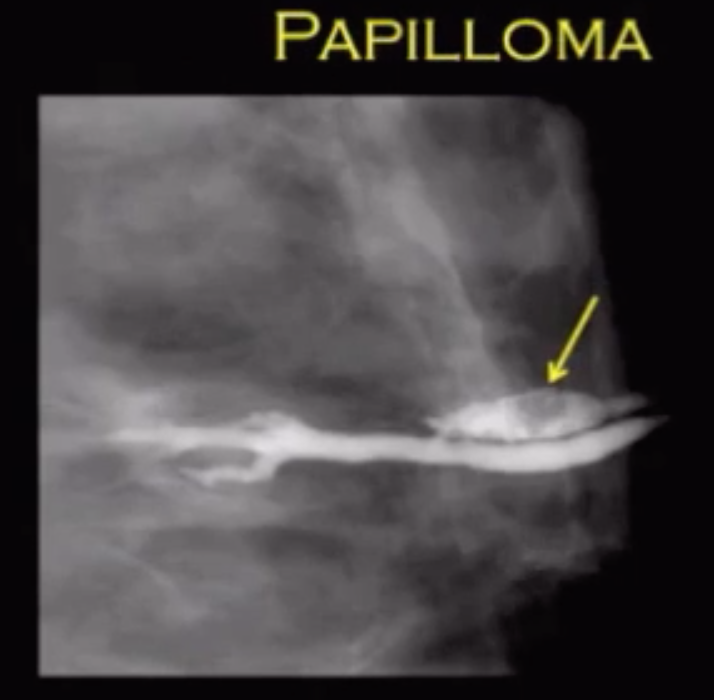

Papilloma

• Most common intraductal mass

• Most common cause of bloody nipple discharge

• Solitary filling defect on galactography

• Usually within 1 cm of nipple

• Multiple filling defects in a duct (note that papilloma will present as a solitary filling defect)

• Multiple intraductal masses/filling defects on galactogram